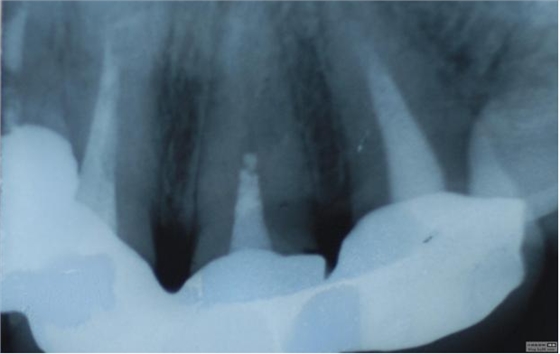

病例1 由于根管充填不完善造成修復(fù)體拆除

修復(fù)后出現(xiàn)根尖周炎癥狀 根管再治療后病變愈合

最近接到這樣一位患者,上前牙氧化鋯聯(lián)冠修復(fù)不足一年時間,現(xiàn)患者主訴左上前牙疼痛來診,檢查發(fā)現(xiàn)上前牙冷熱無反應(yīng),扣診(++),牙齦紅腫,探出血,冠邊緣不密合, X片示基牙全部已做根管治療,但是根管充填全部欠填。